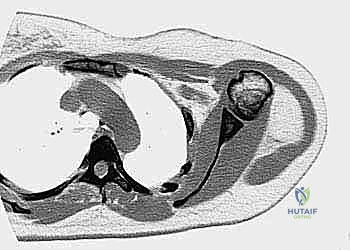

- الأشعة المقطعية (CT Scan): ضرورية لتقييم القشرة العظمية والتكلسات داخل الورم، وللبحث عن أي انتشار في الرئتين.

2. التوجيه الإشعاعي الدقيق

لضمان أخذ العينة من الجزء الأكثر تمثيلاً للورم وتجنب المناطق الميتة (Necrotic areas)، يستخدم الدكتور هطيف جهاز الأشعة المقطعية أو جهاز القوس المفلور (C-arm) لتوجيه الإبرة في الوقت الفعلي.